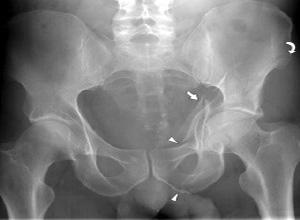

髋臼骨折大多数是由股骨头受到外界暴力传导引起的,常会遗留以下三种并发症:

3、创伤后关节炎

创伤后关节炎是髋臼骨折的远期并发症,多见于髋臼上臂骨折和髋关节后脱位。其发生原因与股骨头承重面骨折、永久性关节半脱位、关节面不对称等因素有关,手术治疗时尽量恢复良好的解剖复位,尤其是髋臼负重面的解剖复位可以有效的降低创伤后关节炎的发生率。